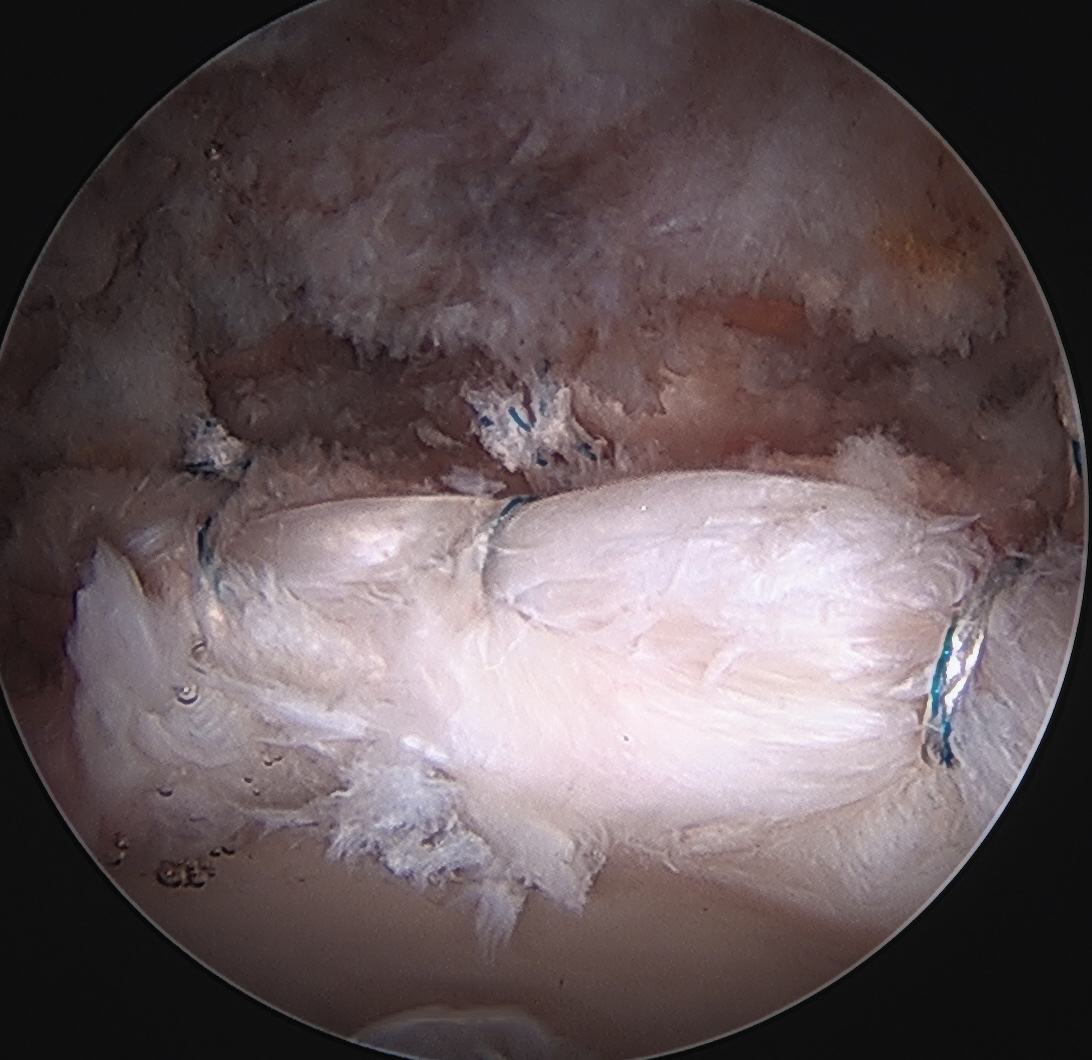

Labral repair

Options

- knotted versus knotless anchors

- straight versus curved

Must avoid intra-articular penetration